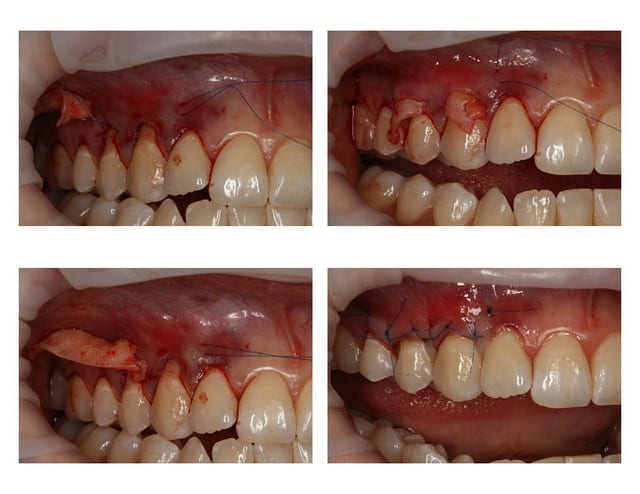

Le p'tit cas du vendredi

Conjonctif placé en tunnel

La suite dans 14 jours

Greffe 13 14  1  zryqqw - Eugenol

Greffe 13 14  2  d0zjrv - Eugenol